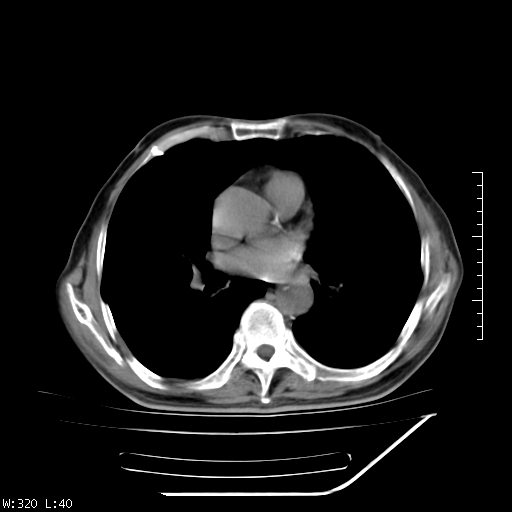

标题: CT23994:男、72、咳嗽、气短两月余,近来消瘦。 [打印本页]

标题: CT23994:男、72、咳嗽、气短两月余,近来消瘦。

右上肺实变,与胸膜关系密切,右肺容积缩小,隆突下淋巴结增大,考虑1 肺结核 2 肺癌

右上肺大片状密度增高影,与胸膜关系密切,内见低密度透亮影,胸膜下可见三角形不张影,左下肺沿支气管走形结节影,纵膈内淋巴结显示。考虑结核并疤痕性不张可能性大,建议穿刺活检,排除肺泡癌。